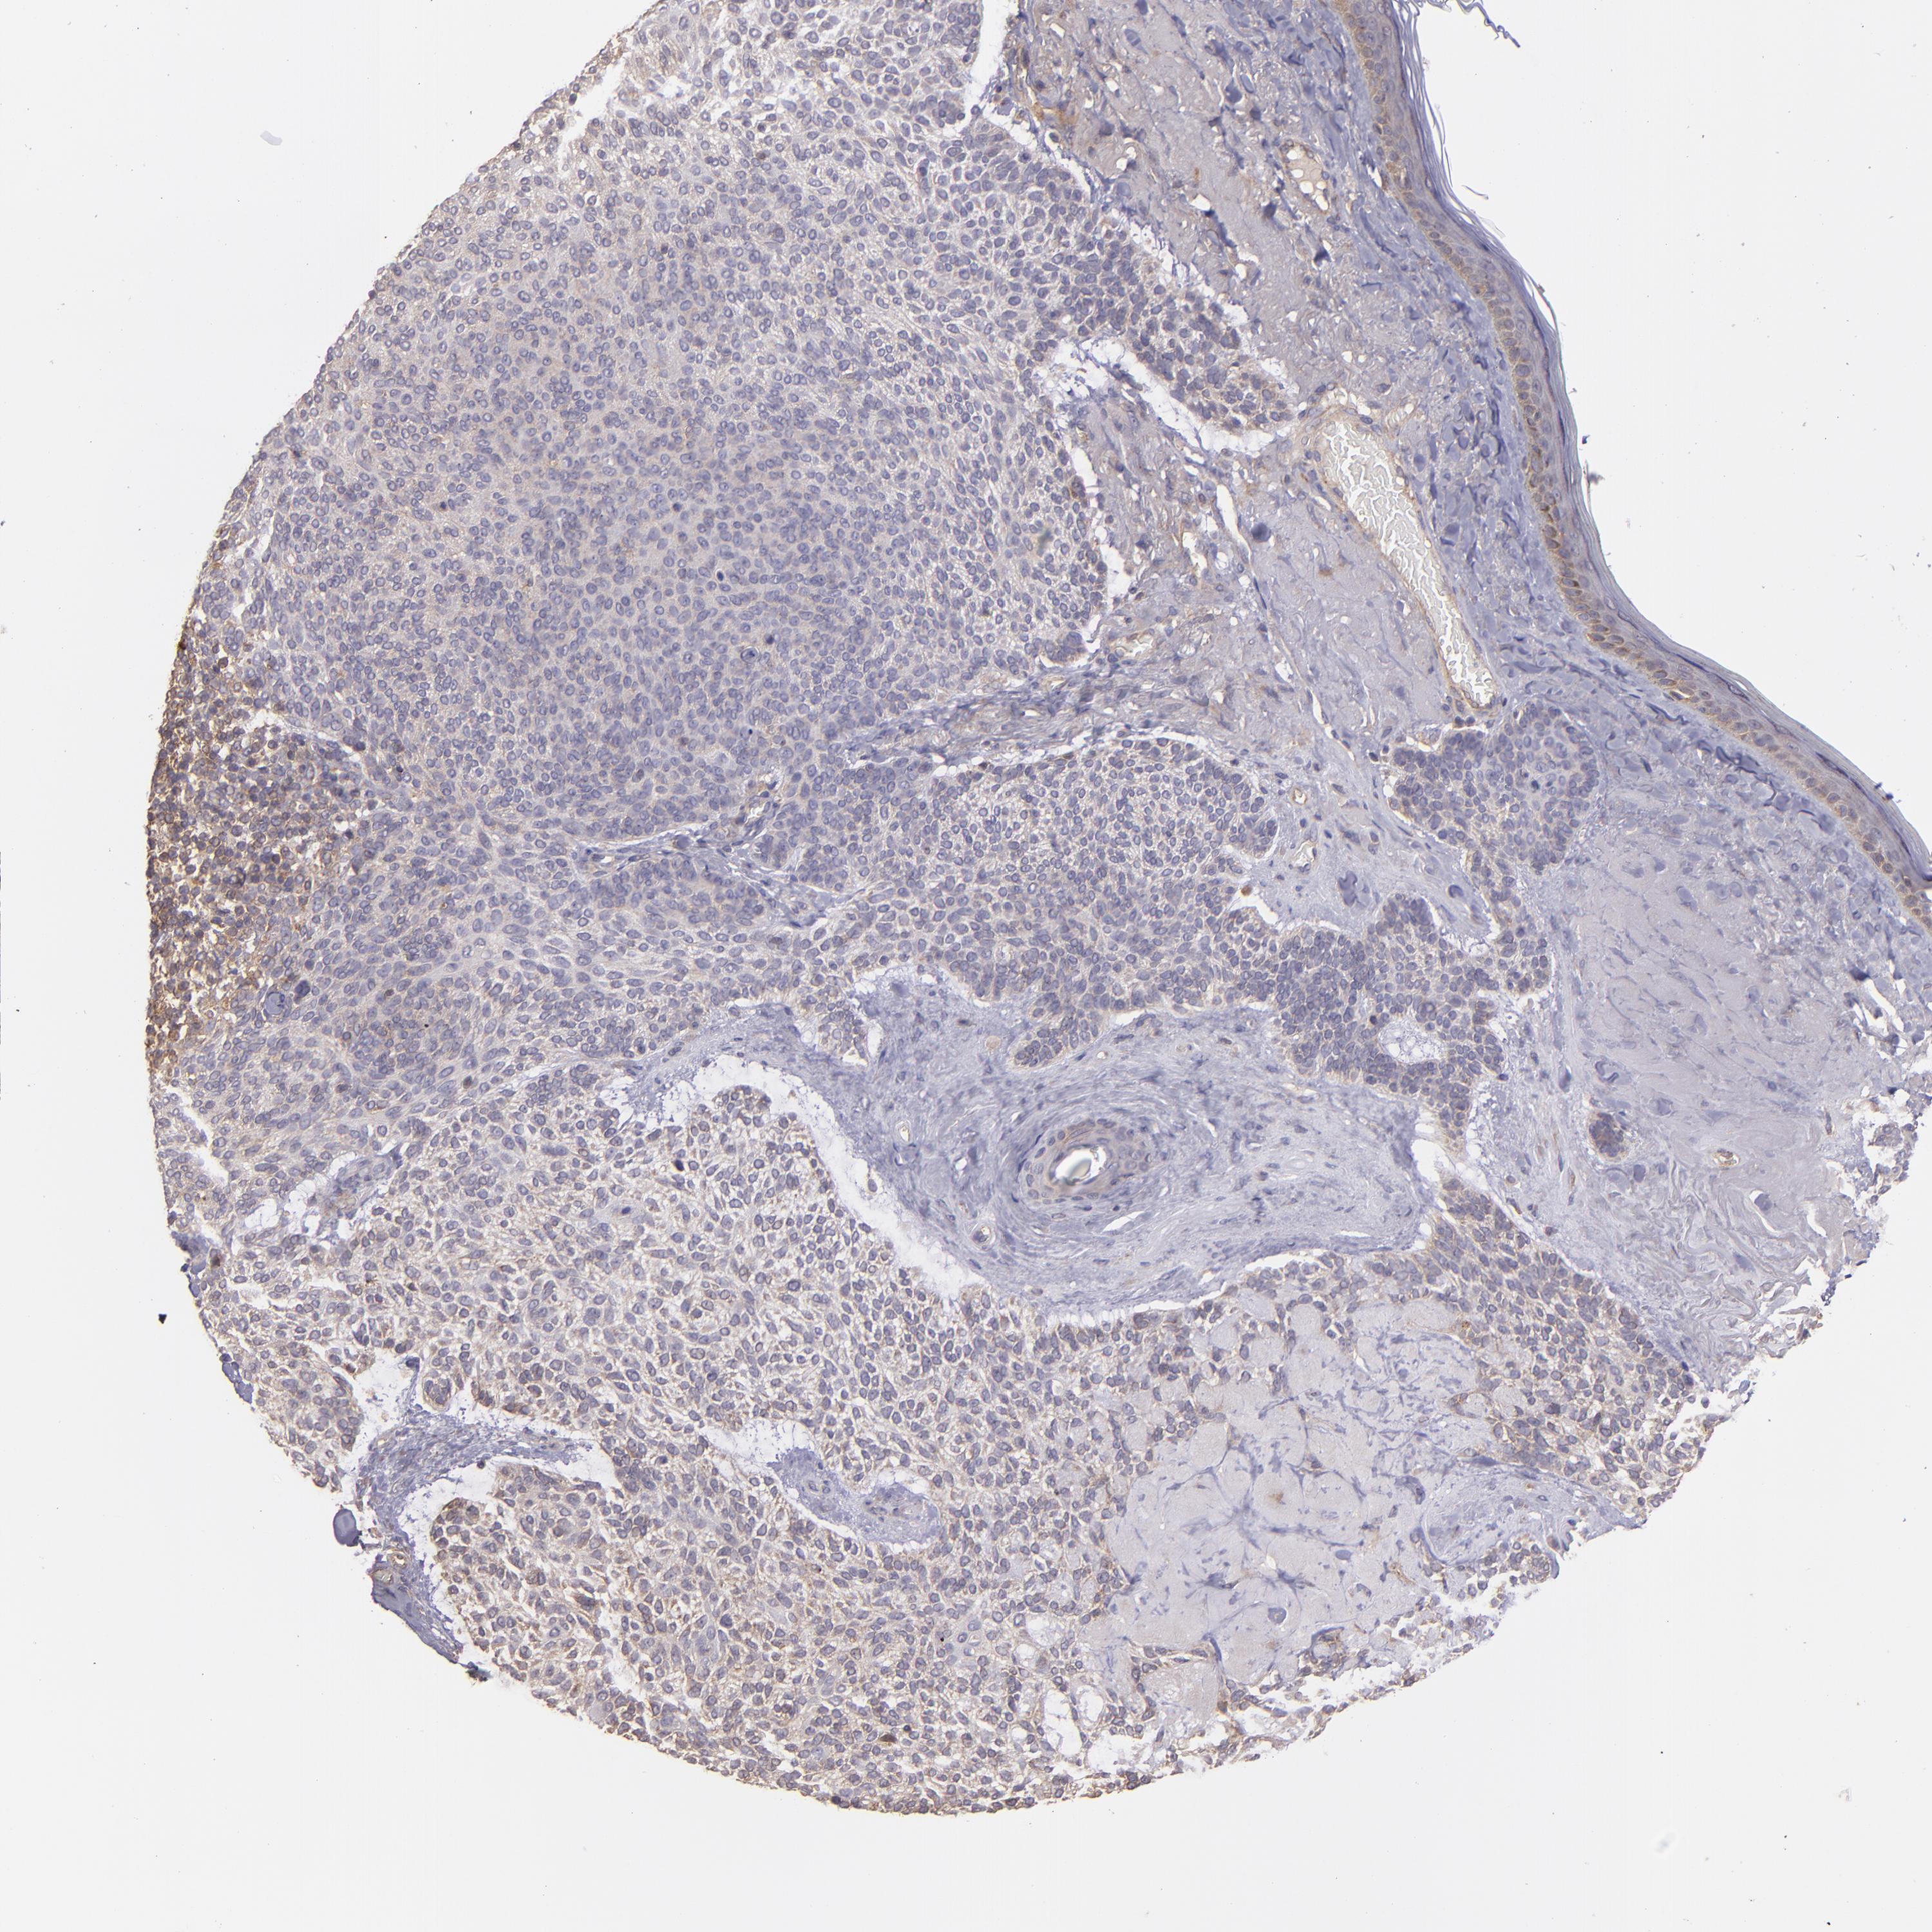

SKIN CANCER - Protein expressioni

A mouse-over function shows sample information and annotation data. Click on an image to view it in a full screen mode. Samples can be filtered based on level of antibody staining by selecting one or several of the following categories: high, medium, low and not detected. The assay and annotation is described here.

Each image is clickable and will lead to virtual microscopy that enables deeper exploration of all samples and also displays staining intensity scores, fraction scores and subcellular localization as well as patient and tissue information for each sample.

Antibody HPA013616

Squamous cell carcinoma, NOS